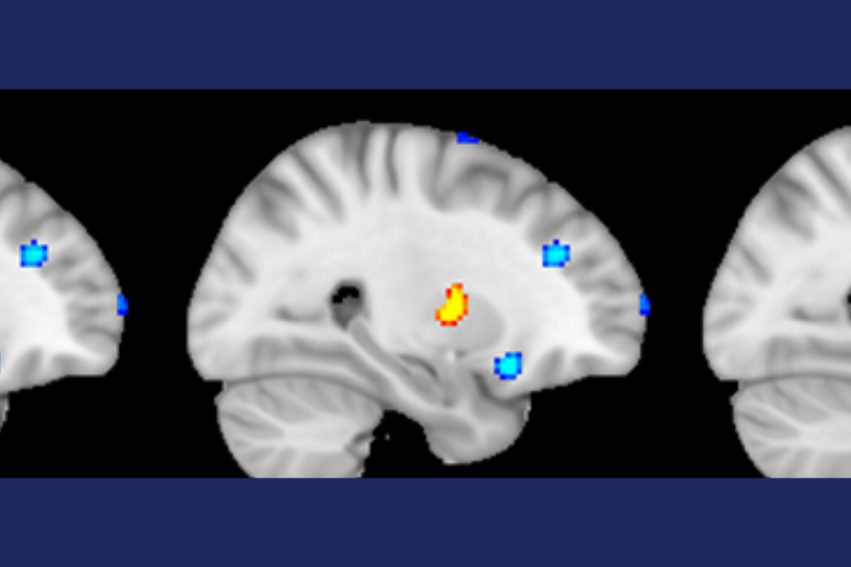

Volume of grey brain matter significantly lower in people with Early Onset Psychosis

Neuroimaging